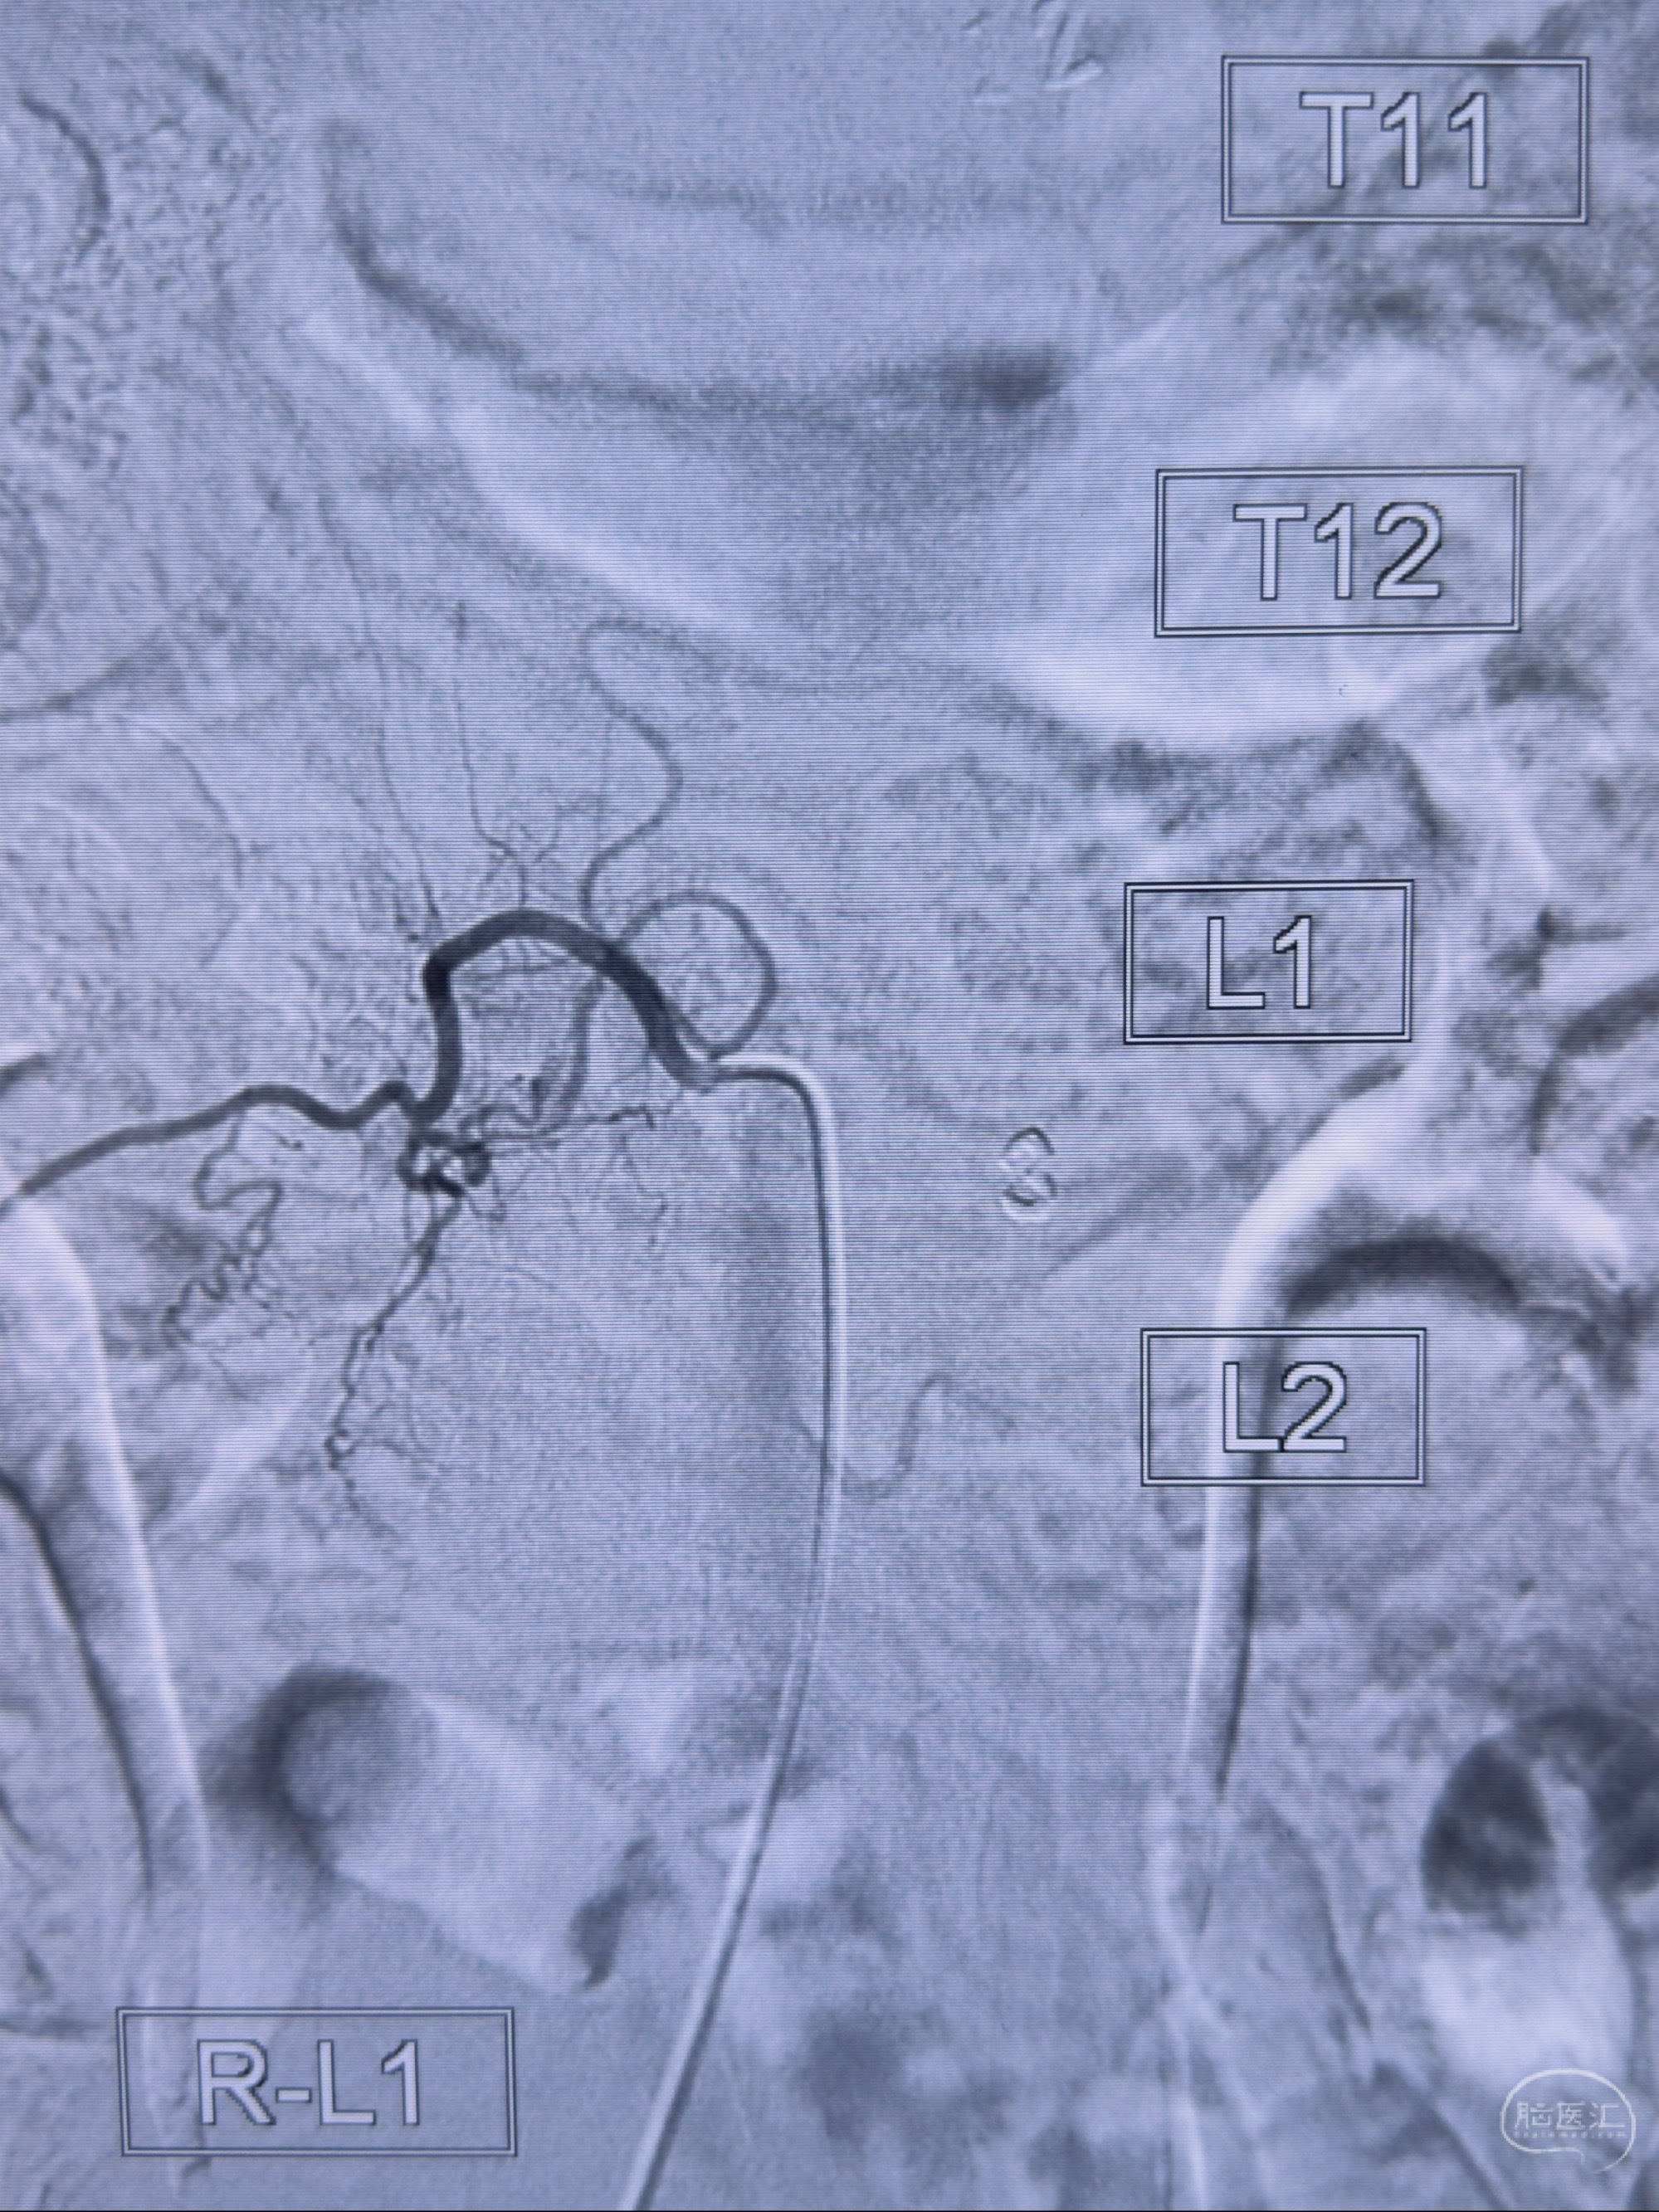

2023-10-13DSA:右侧L1水平硬脊膜动静脉瘘,供血动脉为右侧L1,附近动脉未见明确吻合供血,供血动脉处可见脊髓前动脉发出